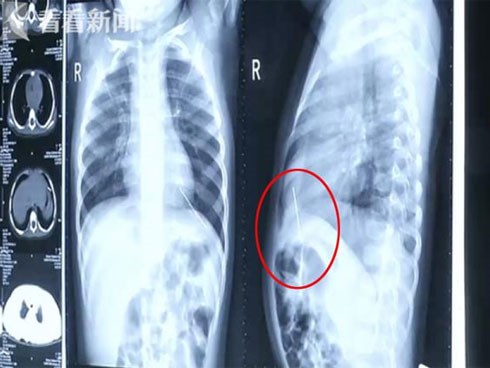

Con ho không ngừng suốt nhiều ngày, mẹ đưa đi khám tá hỏa phát hiện thứ kinh khủng trong ngực

Ban đầu, bố mẹ của bé gái này cứ nghĩ con mình bị ho mãn tính nên đã dùng thuốc tự điều trị. Tuy nhiên, bệnh tình của cô bé không hề dứt mà ngày càng trầm trọng hơn. Khi họ đưa con tới bệnh viện, mọi chuyện mới vỡ lẽ.